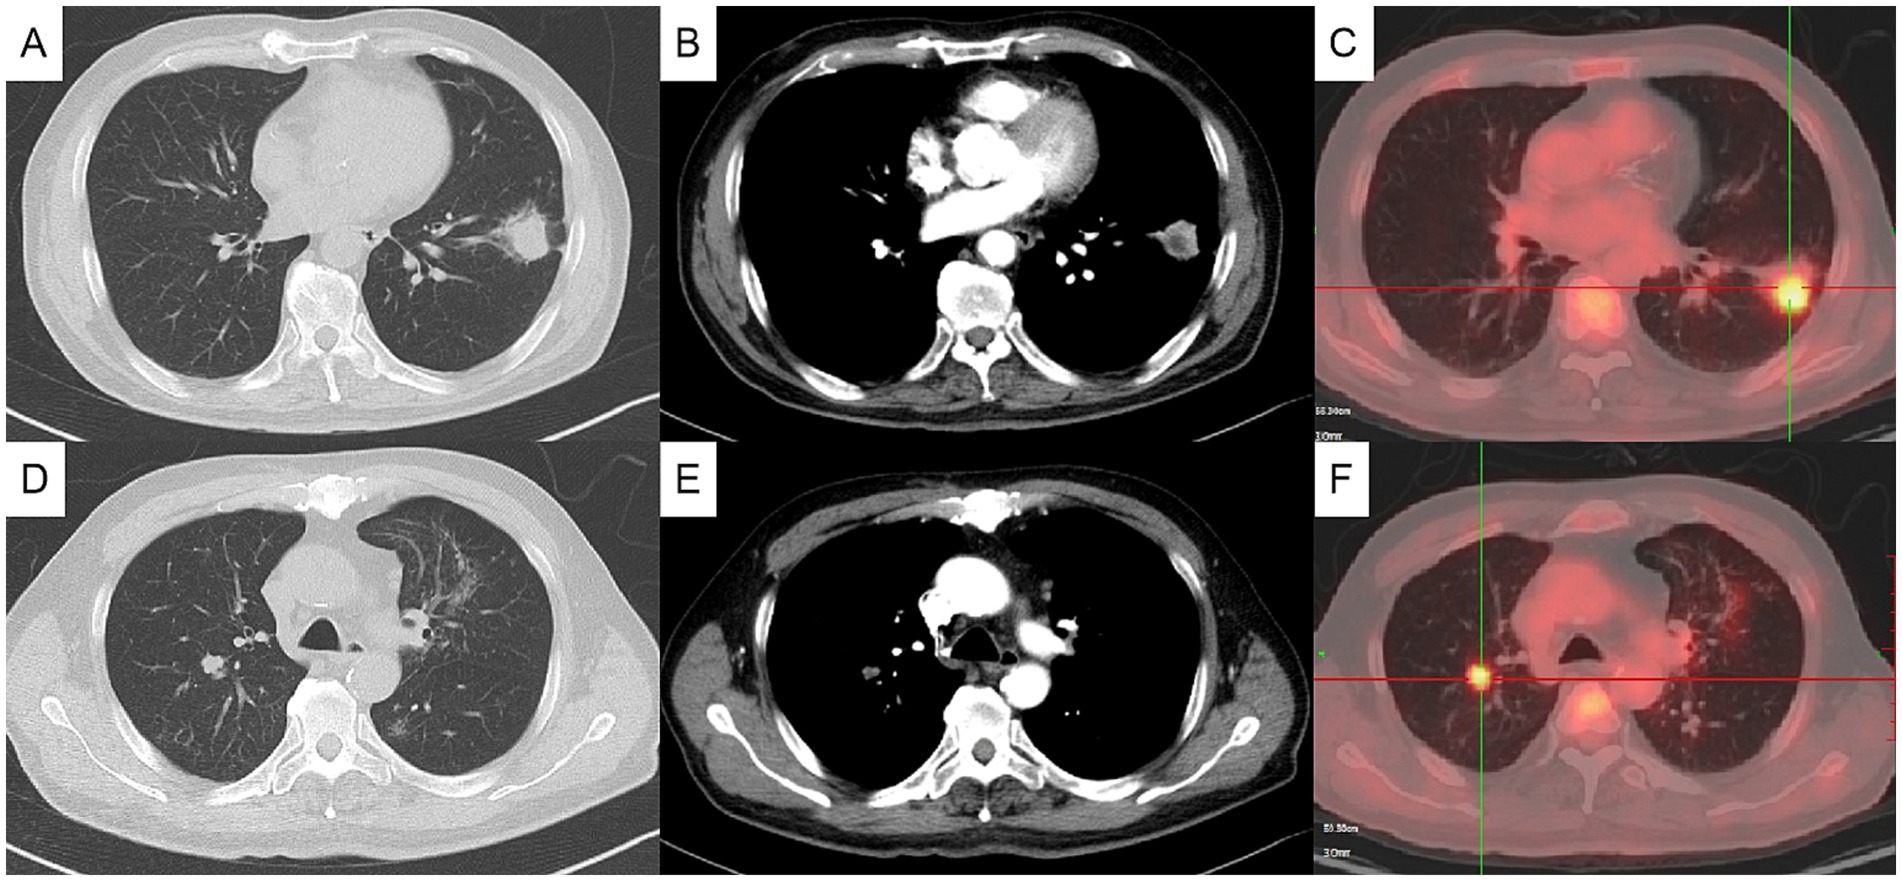

Figure 1

CT and PET scan images of a chest showing a series of slices labeled A to F. Panels A and D depict CT slices of lung tissue with distinct areas that could indicate abnormalities. Figures B and E mainly show the CT images of the mediastinal tissue that could indicate abnormalities. Panels C and F are PET scans with color highlights, where red areas suggest increased metabolic activity, possibly indicating abnormal growths.

Figure 1. Initial chest computed tomography (CT) and positron emission tomography/computed tomography (PET/CT) (axial). Chest CT showing a mass in the anterior and inner basal segment of the left lower lobe, about 3.1×2.5 cm, with signs of lobulation, burr, pleural adhesion and local bronchial truncation (A,B). Chest CT showed multiple small patch shadows around the bronchi of the right upper lobe and small solid nodule in the posterior segment of the right upper lobe, appropriate 1 cm in size (D,E). PET/CT indicating hypermetabolism in the nodules of the left lower lung (C) and the right upper lung (F), with SUVmax value of 5.7 and 4.7, respectively. (A, C pulmonary window, B, D mediastinal window).

The physical examination showed no abnormality. The complete blood count, C-reactive protein (CRP), procalcitonin, erythrocyte sedimentation rate (ESR), G test, GM test, and tumor markers including CEA, SCC, CA125, pro-GRP and NSE were normal. T-SPOT was positive. Chest computed tomography (CT) depicted a 3-cm mass in the left lower lobe (Figures 1A,B) and a 1-cm nodule in the right upper lobe (Figures 1D,E). Positron emission tomography-computed tomography (PET/CT) indicated hypermetabolism in the left mass (SUVmax 5.7) (Figure 1C) and right nodule (SUVmax 4.7), both suggestive of malignancy (Figure 1F). The patient underwent a CT-guided percutaneous lung puncture biopsy of the left lower lobe mass. Pathological results revealed severe chronic active inflammation. Nodular amorphous necrotic substances were observed locally, containing thin rod-shaped thalli of varying lengths, some of which were clustered, indicative of actinomycosis (Figure 2C). Weak acid-fast staining of lung tissue was negative. Based on these findings, the patient was diagnosed with pulmonary actinomycosis. β-Lactams are recommended as first-line treatment of actinomycosis (7). Oral amoxicillin-clavulanate potassium (amoxicillin 0.2 g, clavulanate potassium 28.5 mg) were used empirically. The patient were prescribled 4 tablets orally twice daily, with a follow-up chest CT planned after 1 month. In addition, elevated blood glucose levels were detected during hospitalization, with glycosylated hemoglobin of 7.8%. He was diagnosed with type 2 diabetes, and started on hypoglycemic therapy.